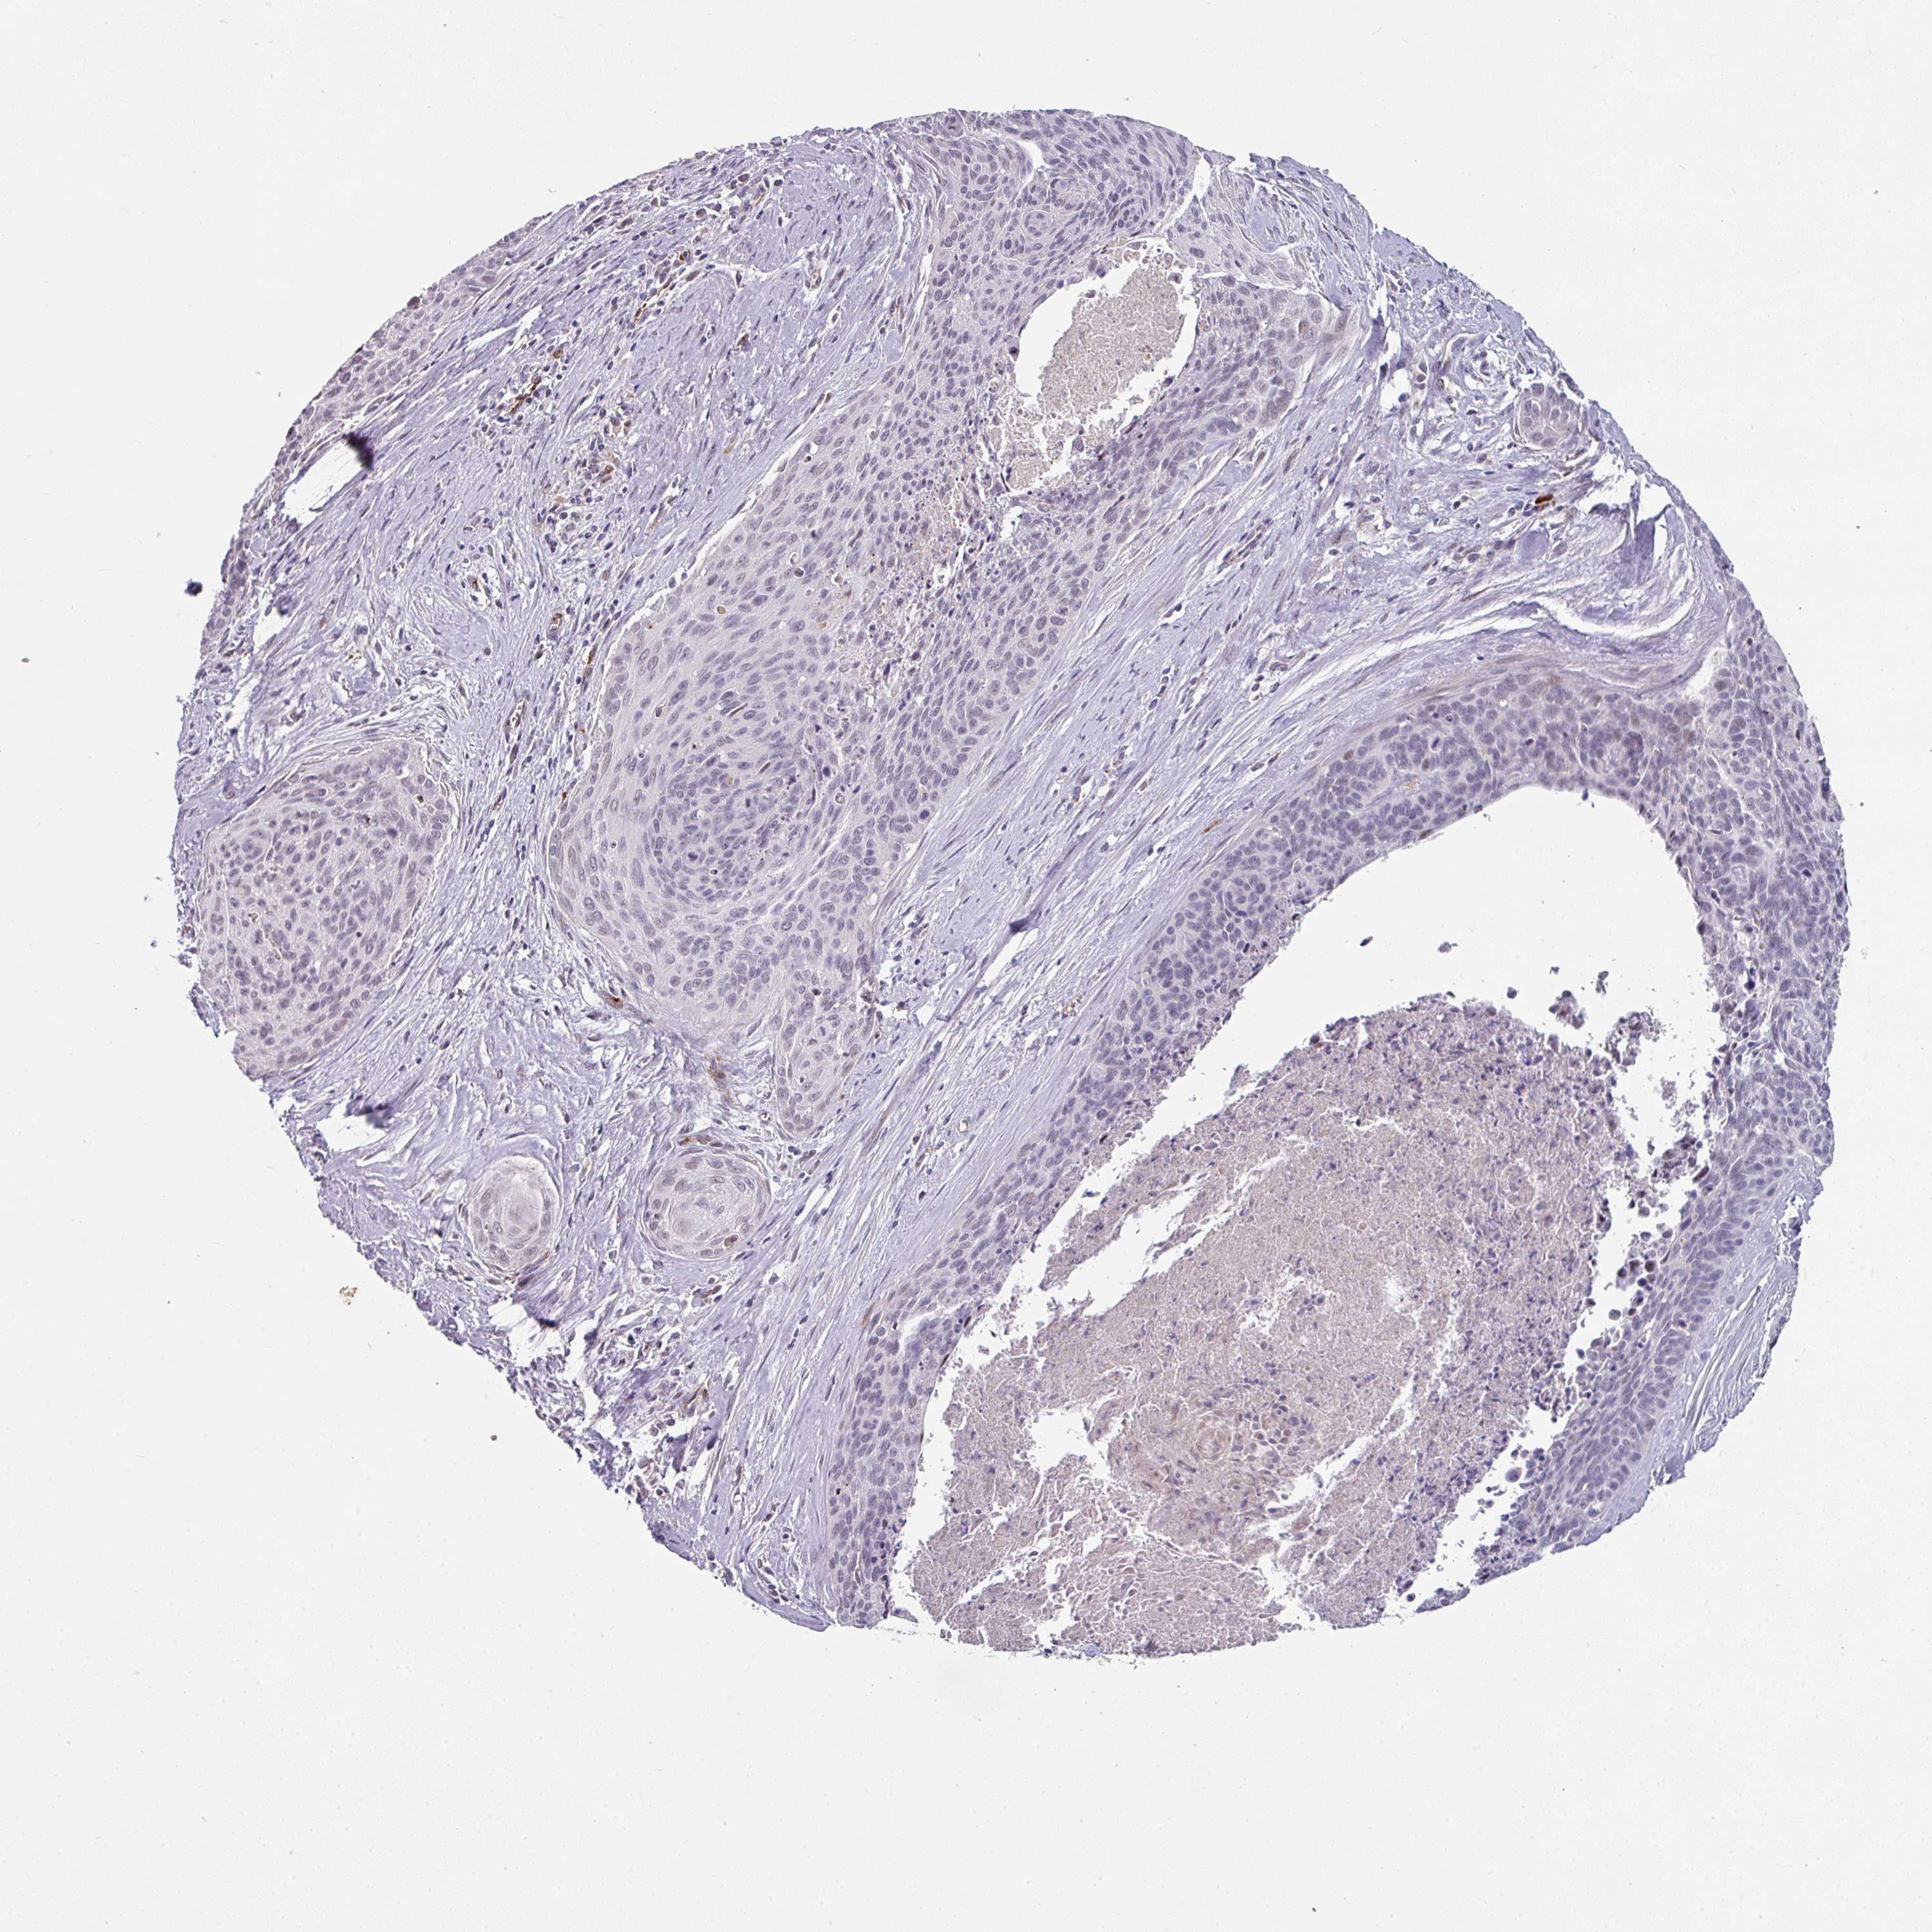

CERVICAL CANCER - Protein expressioni

A mouse-over function shows sample information and annotation data. Click on an image to view it in a full screen mode. Samples can be filtered based on level of antibody staining by selecting one or several of the following categories: high, medium, low and not detected. The assay and annotation is described here.

Note that samples used for immunohistochemistry by the Human Protein Atlas do not correspond to samples in the TCGA dataset.

Antibody stainingi

Antibody staining in the annotated cell types in the current human tissue is reported as not detected, low, medium, or high, based on conventional immunohistochemistry profiling in selected tissues. This score is based on the combination of the staining intensity and fraction of stained cells.

Each image is clickable and will lead to virtual microscopy that enables deeper exploration of all samples and also displays staining intensity scores, fraction scores and subcellular localization as well as patient and tissue information for each sample.

Antibody HPA052352

Staining

High

Medium

Low

Not detected

Intensity

Strong

Moderate

Weak

Negative

Quantity

>75%

75%-25%

<25%

None

Location

Nuclear

Cytoplasmic/membranous

Cytoplasmic/membranous,nuclear

Squamous cell carcinoma, NOS

Adenocarcinoma, NOS